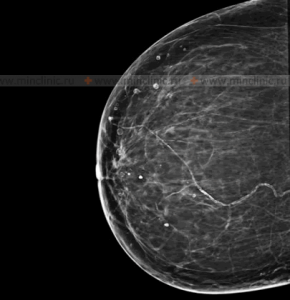

Многокамерная киста молочной железы может перейти в рак, почему?

Многокамерная киста молочной железы представляет собой опухоль, образующуюся из молочных протоков и железистой ткани. В большинстве случаев кисты являются доброкачественными образованиями и не представляют угрозы для здоровья. Однако, в некоторых случаях многокамерная киста может стать преканцерозным состоянием, что означает, что она может быть предвестником рака молочной железы.

Есть несколько причин, почему многокамерная киста может перейти в рак:

1. Нарушение клеточного деления: В некоторых случаях клетки лининга кисты могут начать не контролируемо делиться, что может привести к развитию злокачественной опухоли.

2. Наличие предраковых изменений: В многокамерных кистах могут образоваться предраковые изменения, такие как атипичные клетки, которые могут впоследствии прогрессировать в рак.

3. Длительное существование кисты: Чем дольше многокамерная киста существует, тем больше возможность, что в ней могут происходить изменения, приводящие к развитию рака.

4. Генетические факторы: Наследственные мутации могут также увеличить вероятность того, что многокамерная киста прогрессирует в рак молочной железы.

В целом, хотя большинство многокамерных кист являются доброкачественными, важно следить за их состоянием и своевременно обращаться к врачу для диагностики и наблюдения за ними, чтобы свести к минимуму риск их прогрессирования в рак.